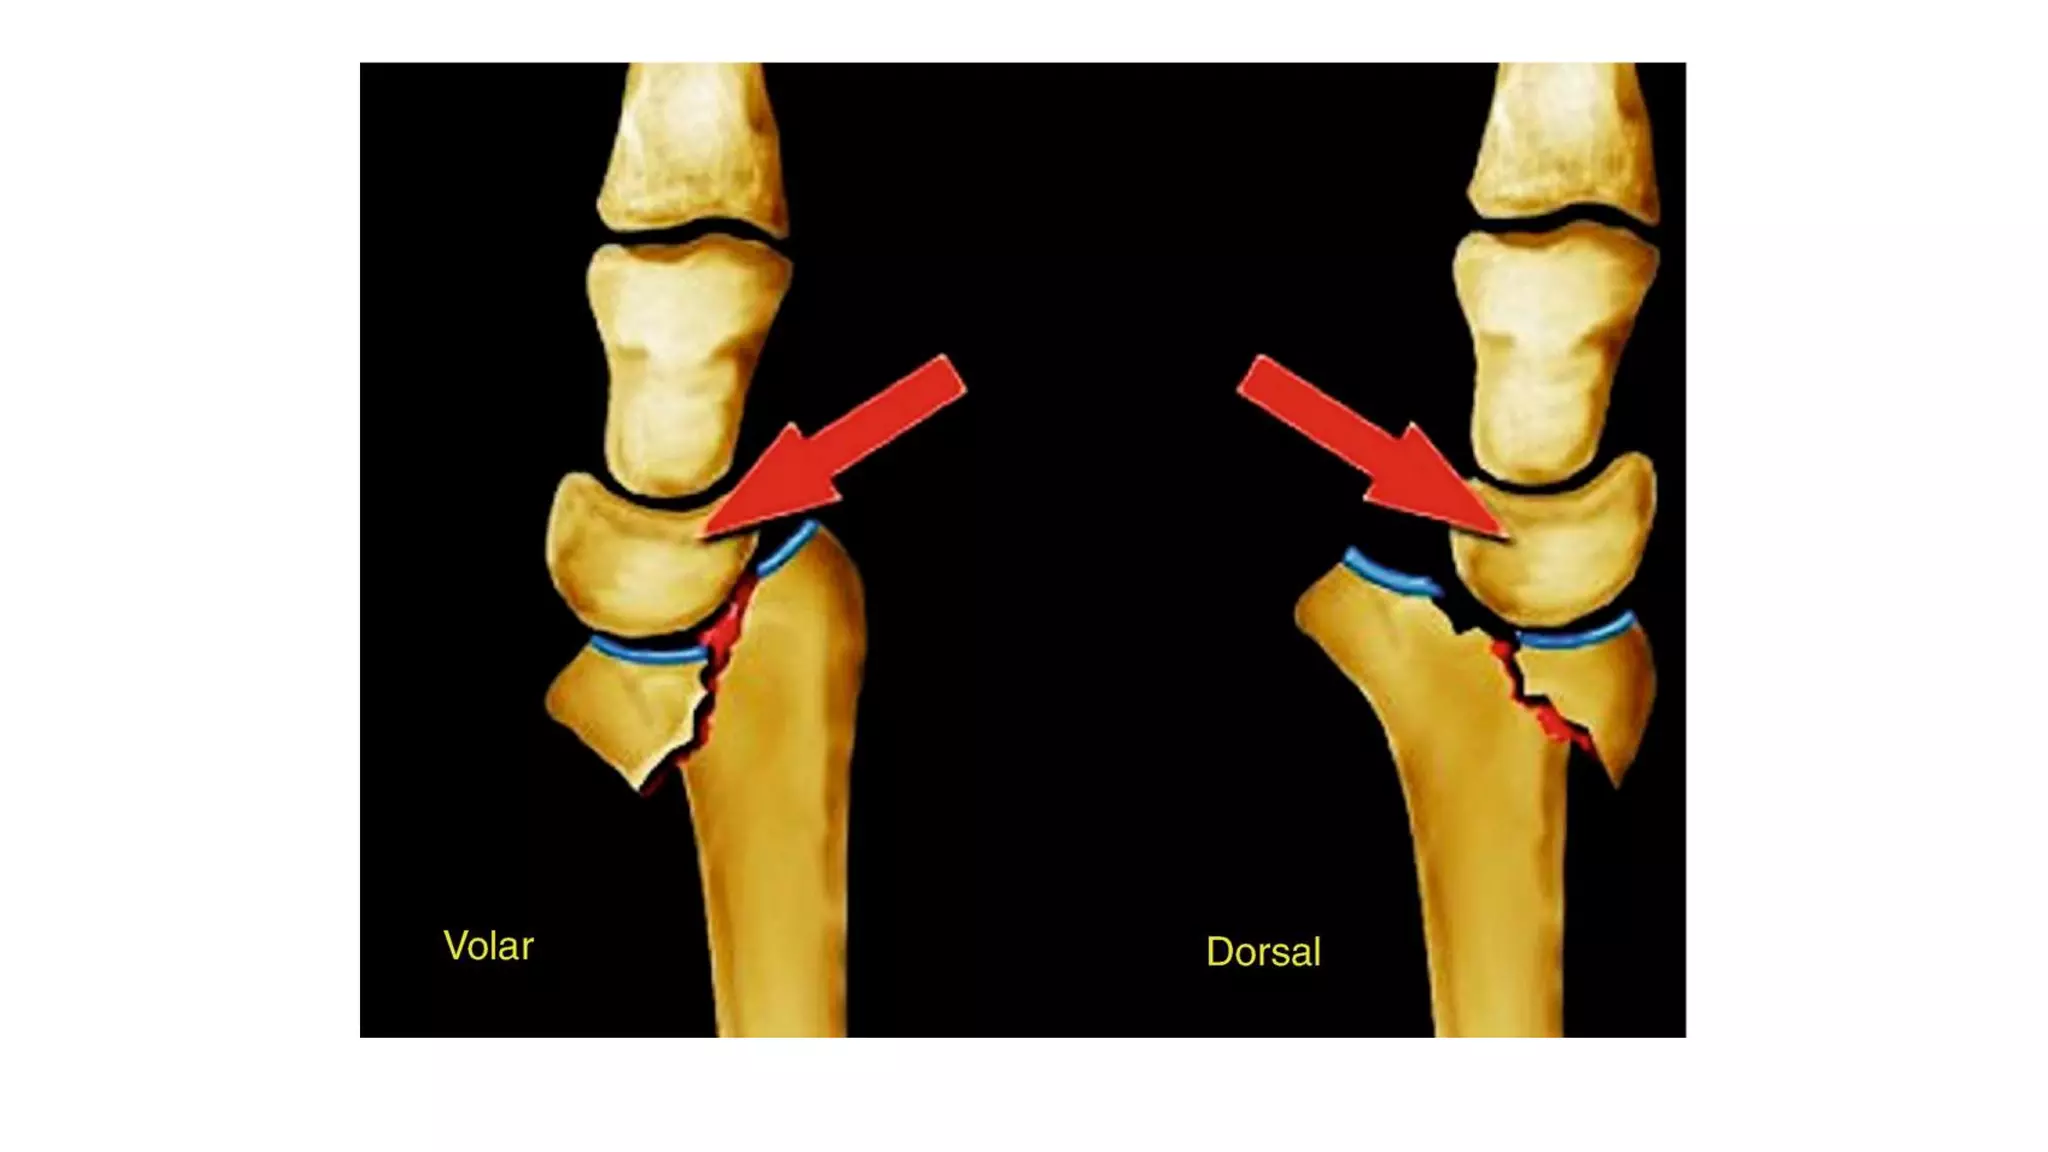

Volar Barton fracture

Rim avulsion fracture of the distal radius in which volar half of the

distal radius shear off with intact dorsal half & the fragment moves

forwards carrying the carpus with it.

Mechanism:

• It is due to palmar tensile stress and dorsal shear stress and is usually

combined with Radial styloid fracture.